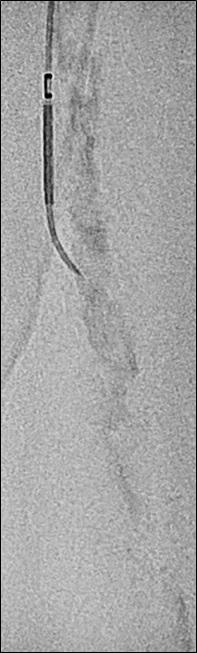

n PERIPHERAL ARTERIAL DISEASE:

Crossing chronic total occlusion lesions are challenging procedures. The BeBack crossing catheter—Bentley’s first product to be available in both Europe and the USA following the company’s acquisition of Upstream Peripheral Medical Technologies’ GoBack crossing catheter in September 2022— offers a new solution in this space. In a Bentleysponsored advertorial, Andrej Schmidt (Leipzig, Germany) shares his clinical experience with the BeBack, noting how it has been a “gamechanger” in his endovascular peripheral arterial disease practice.

For more on this story go to page 19.